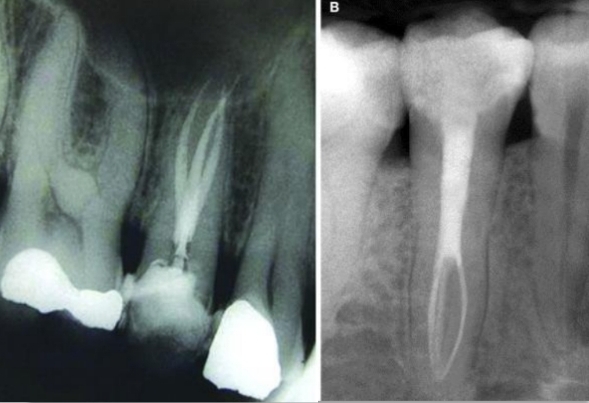

How long may it take for high radiolucency cases take to resolve after RTC?

Up to 2- years

If minimal bone formation after a few months - successful treatment